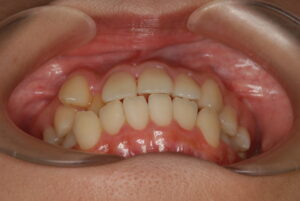

実際の症例紹介(20代女性/裏側ワイヤー矯正)

治療前

治療後

・主訴:八重歯と前歯の突出

・治療法:裏側からのワイヤー矯正(リンガル)

・治療期間:約1年半〜2年(目安)

・予想される副作用・リスク:装置装着後の違和感・疼痛、発音のしづらさ、一時的な咀嚼効率低下、ブラッシング不良によるむし歯・歯周病リスク など

※写真は代表的な症例です。口腔内の状態により治療法や期間は異なります。詳細は初診相談でご説明します。